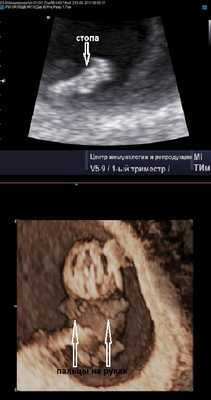

Продолжается развитие эмбриона. Уже отчётливо видны ручки ножки, а на хорошем аппарате порой удаётся разглядеть даже пальчики на руках и ногах. Частота сердцебиения на этом сроке достигает 170-190 ударов в минуту. Шевеления эмбриона становятся активными, и есть работы, показывающие, что чем активнее ребёнок, тем длиннее будет пуповина (хотя тут может быть и обратная зависимость).

Случай острого развития синдрома анемии-полицитемии (TAPS) у монохориальной диамниотической двойни с синдромом селективной задержки роста плода (sIUGR)

Перинатальный центр РКБ МЗ Республики Татарстан, Казанская государственная медицинская академия - филиал ФГБОУ ДПО РМАНПО МЗ РФ, Казань.